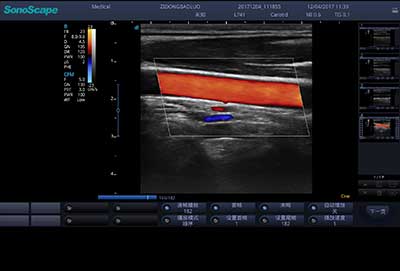

E3便携式彩色多普勒超声诊断系统拥有专业超声技术平台、高度集成化的硬件模块和结构设计、简便的操作流程、支持三探头接口全激活,兼顾了优质图像、轻便机身以及台便两用的临床使用需求。无论在常规超声科门诊检查,还是在急诊、麻醉、ICU、户外等各种应用场景。都能给您带来流程的操作体验。

血管内中膜自动测量